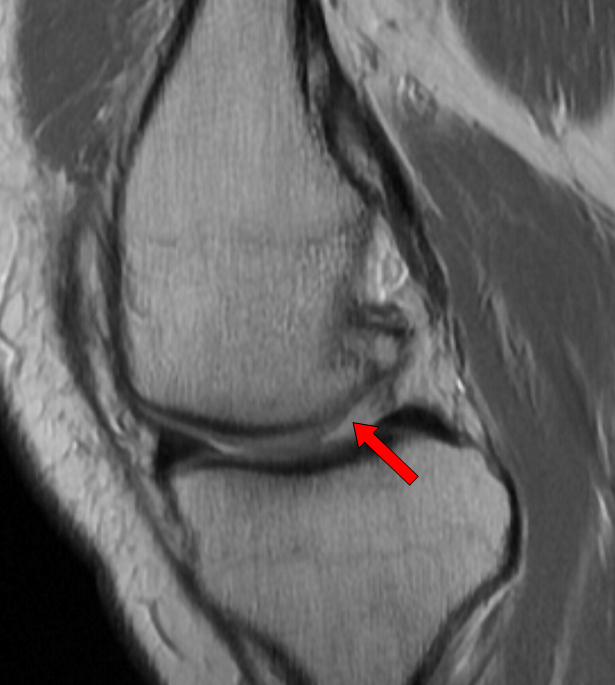

Meniscal Tears

Torn Medial Meniscus. CKC MRI

Horizontal tear of the posterior horn of the medial meniscus with a cyst